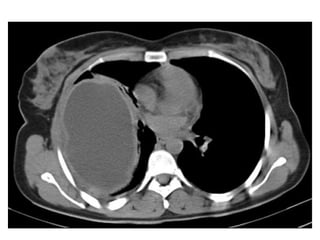

(a) Axial CT scan of an asbestos-exposed person shows a left-sided pleural

effusion (arrow), (b) Axial CT scan obtained 2 years later shows

circumferential pleural thickening that extends into the major fissure (straight

arrow) and contains flecks of calcification (curved arrow)